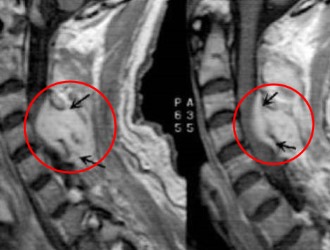

Для диагностики абсцесса спинного мозга применяются методы МРТ и КТ. При наличии острого воспалительного процесса можно заметить изменения в анализах крови, такие как лейкоцитоз и ускорение скорости оседания эритроцитов (СОЭ). В случае хронической формы заболевания выраженные изменения в анализах крови, как правило, отсутствуют.

В рамках стандартного обследования пациенту назначаются КТ и МРТ позвоночника.